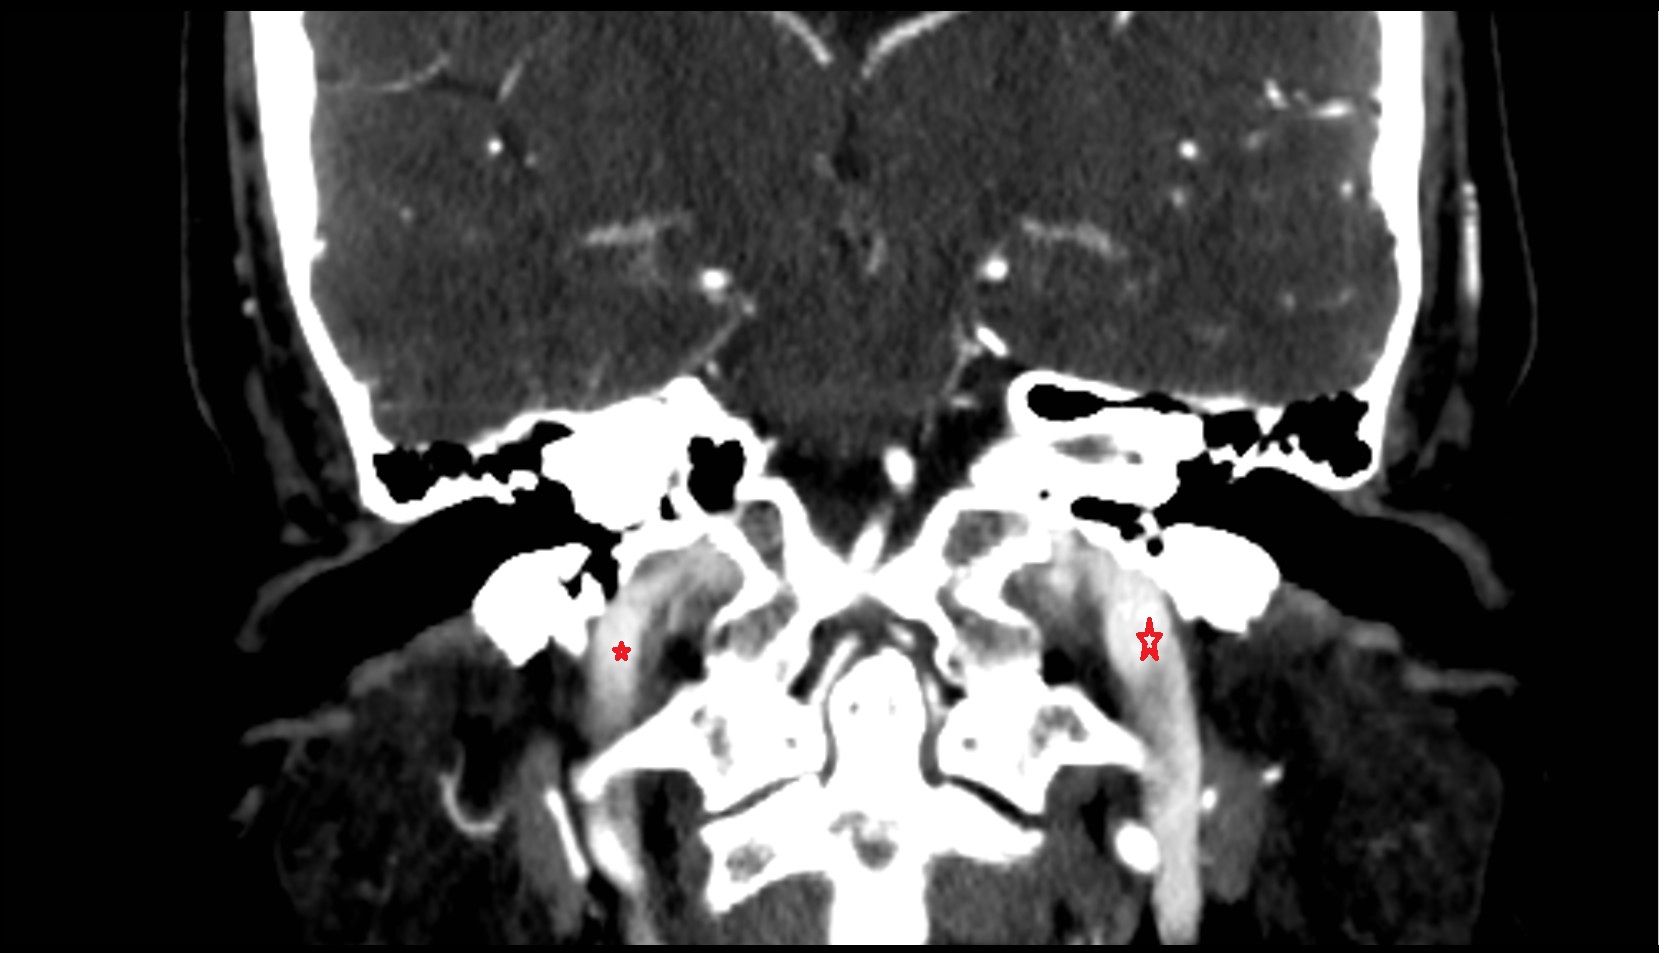

- Carotid bifurcation

- Internal carotid artery (cervical part)

- Superior bulb of internal jugular vein